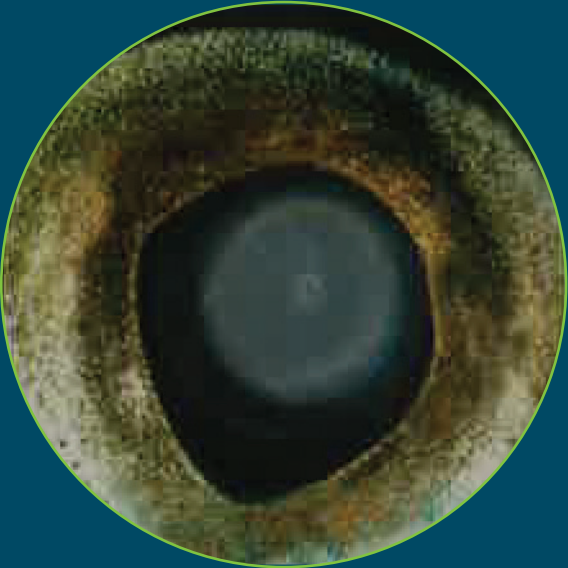

Atlantic salmon eye with moderate opacity17

|